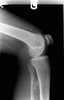

Pachydysostosis of the fibula

Bowed tubular bones